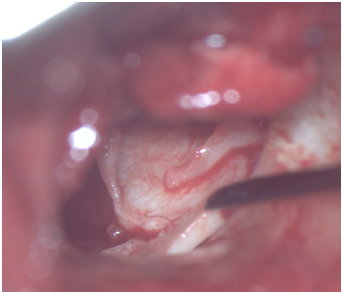

Cartilage shield tympanoplasty (CST) has been described and used in recent times with good success rates.11,12 The technique uses a piece of tragal or conchal cartilage from ear as grafting material and making a notch in its superior aspect to accomodate handle of malleus. Modified version of CST would avoid making a notch and putting the cartilage piece directly lateral to incudo-stapedial (IS) joint, medial to handle of malleus and supporting the graft from medial side by gelfoam pieces (Figure 1).13 Temporalis fascia can also be used in combination with cartilage piece.

Figure 1 Cartilage graft being placed medial to handle of malleus